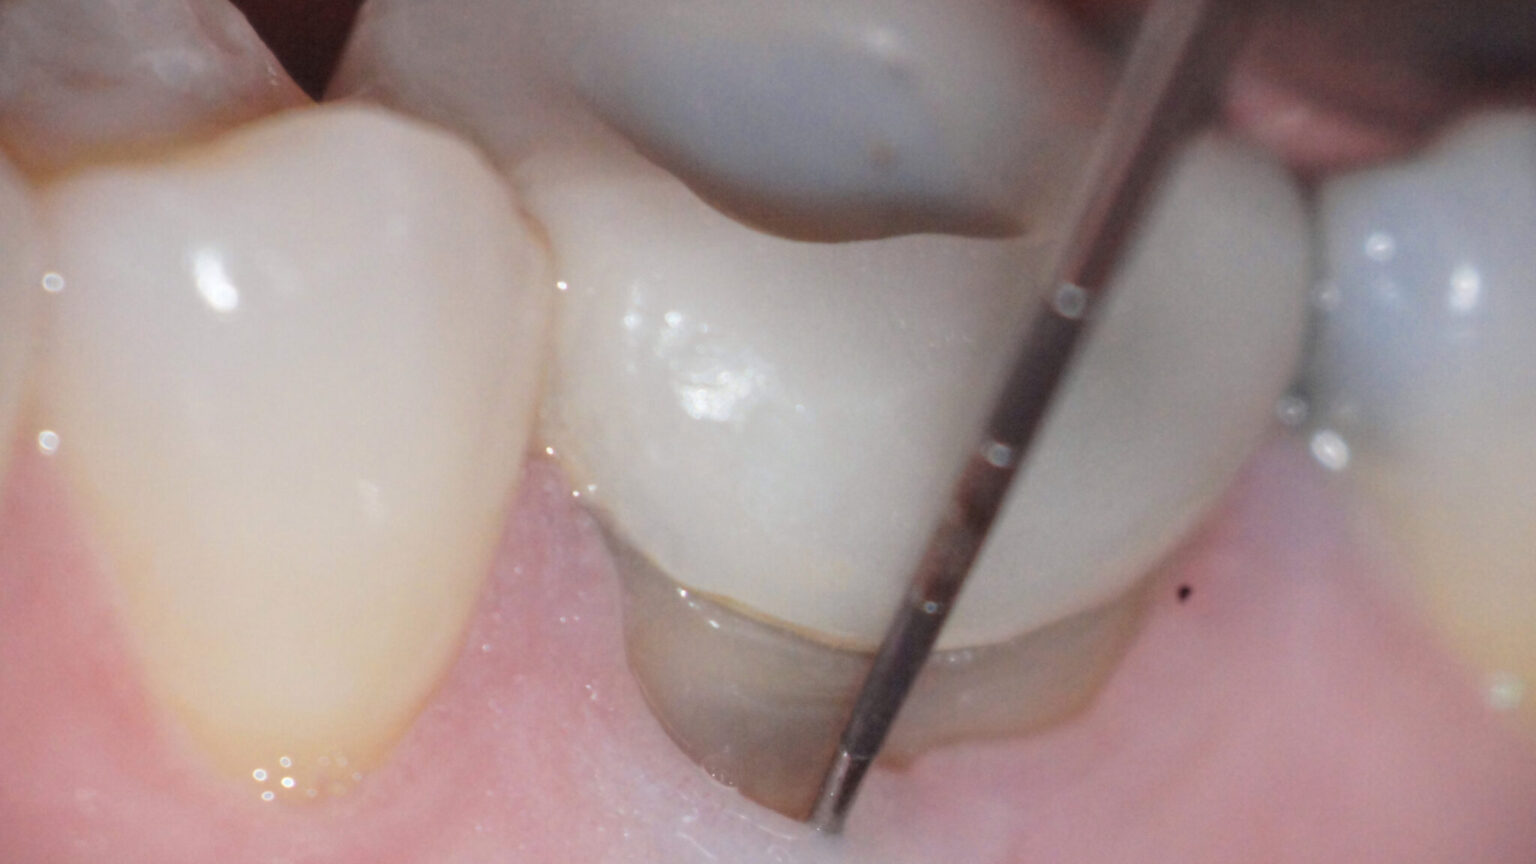

EndodonticPeriodontal Interrelationship Pocket Dentistry What Is Endodontic Posts Removal of tooth structure with these characteristics allows a realistic and necessary appraisal of the amount of viable. What is one and why is it needed? After your tooth’s root canal treatment (endodontic therapy) has been completed, it will be time for. Posts can be used to retain amalgam, metal, and composite cores and help strengthen the connection between the. What Is Endodontic Posts.